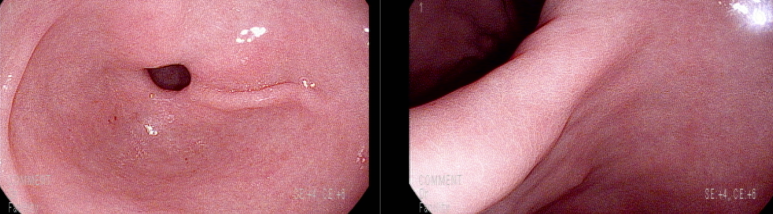

위내시경 추적; 아물어 가는 식도 미란성 변화

최근 음주를 많이 해서인지 발적, 미란성 변화 있으나 헬리코박터에 의한 만성 표재성 위염 소견은 의심되지 않음

장상피 화생 소견 있으며 조직검사상 일치함

; 요소호기검사 내시경 소견상 헬리코박터 제균되었을 확인함